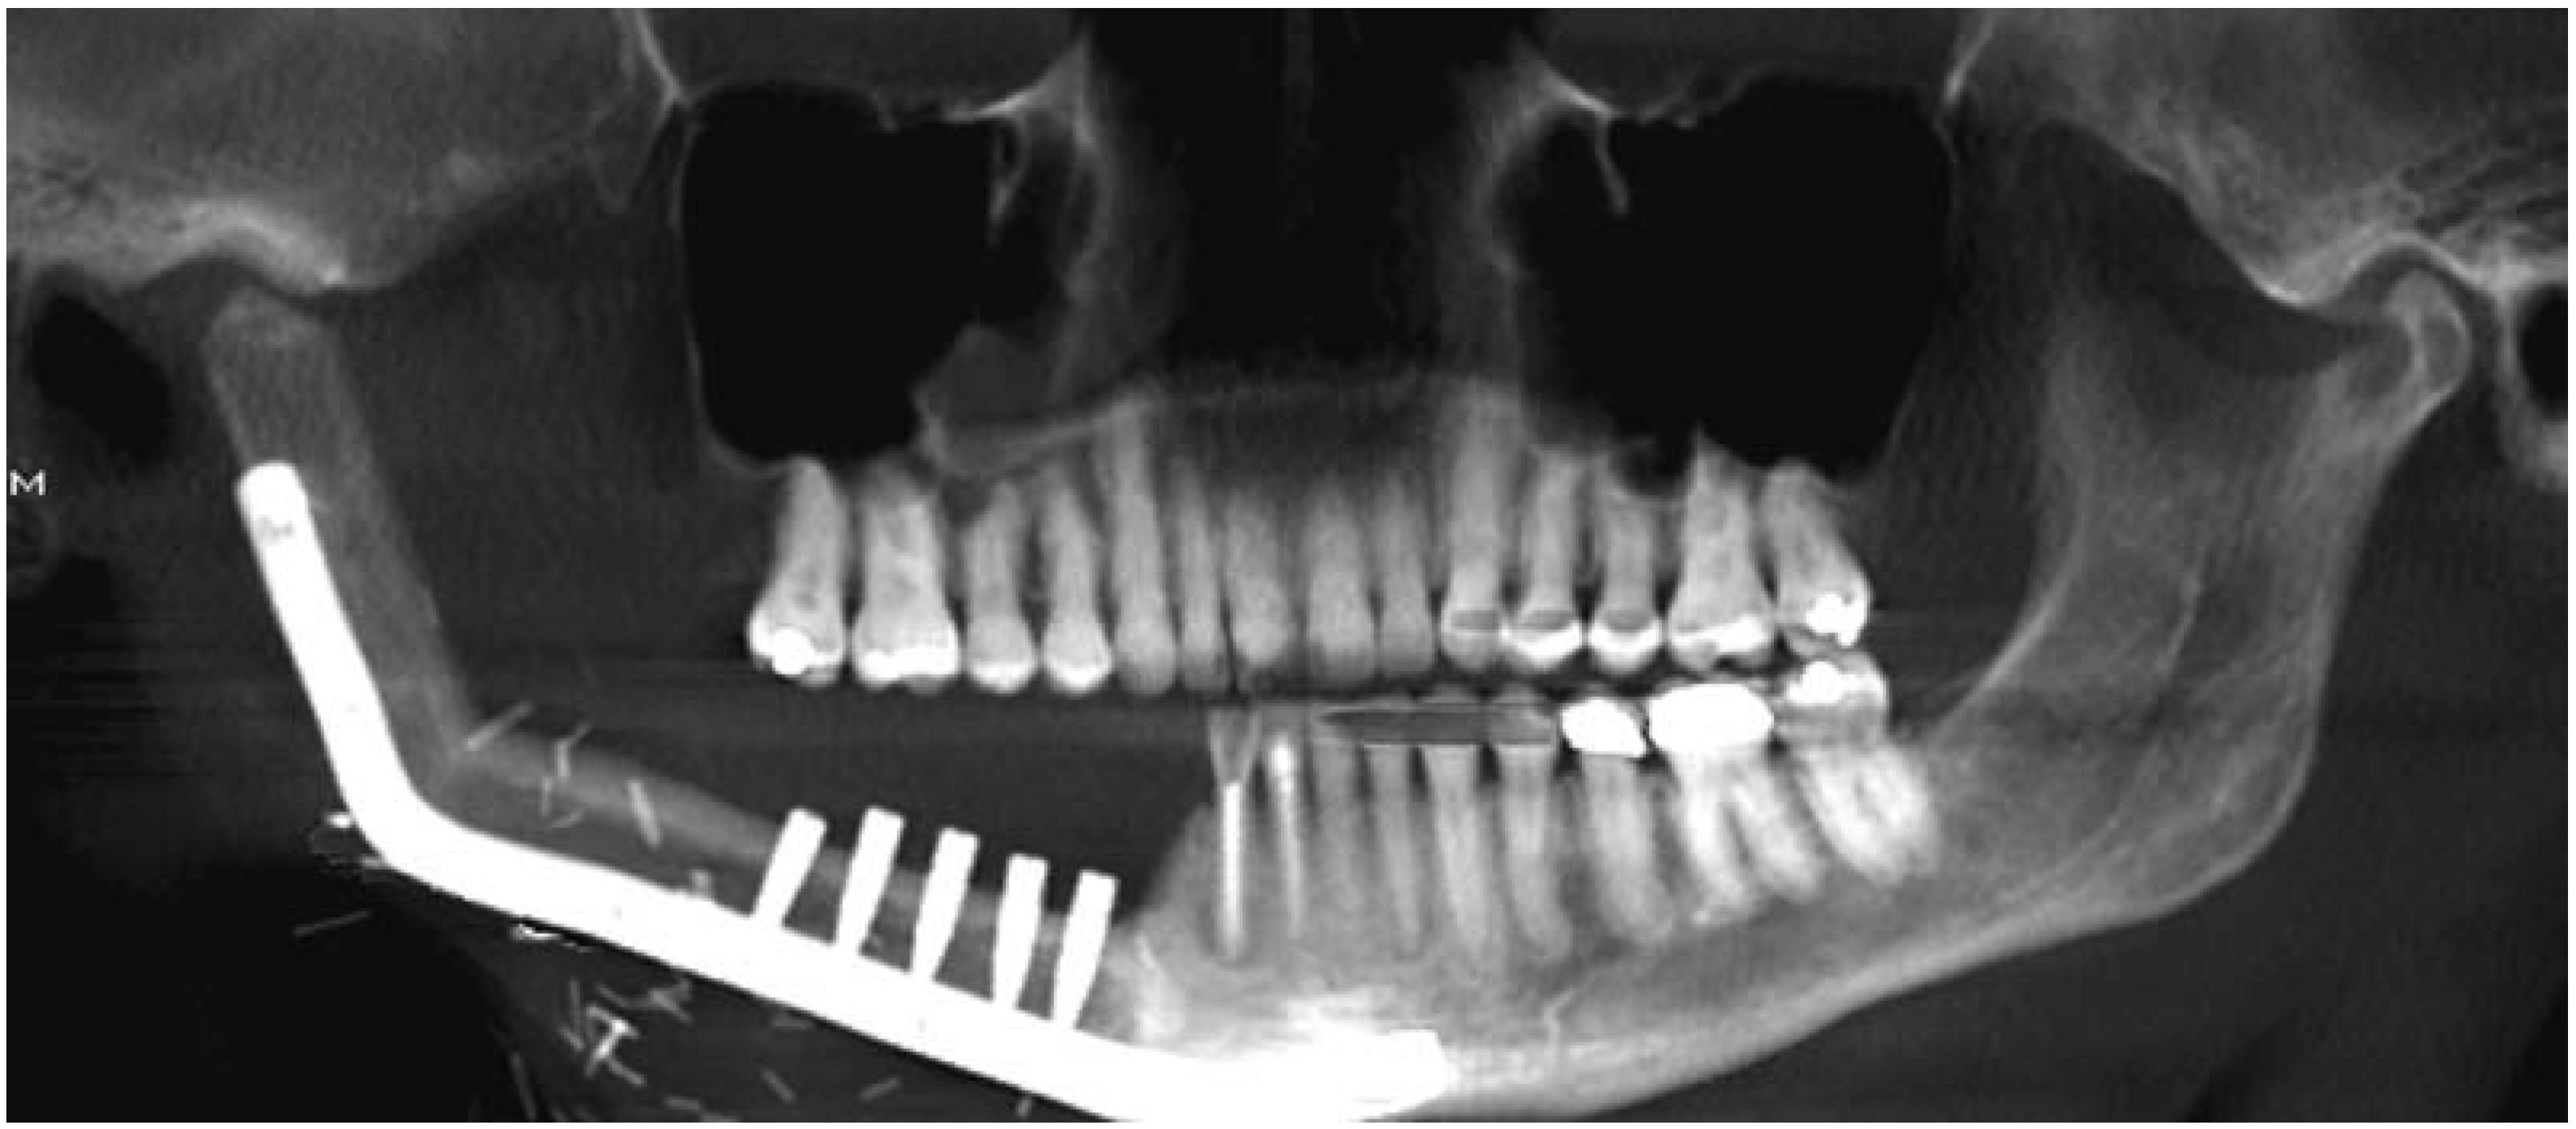

On postoperative day 7, the skin paddle of the fibula free flap appeared bluish/dusky (Figure 1b) with brisk bleeding of dark blood on pinprick. There was complete absence of Doppler signal from skin paddle. There was no change in skin turgor. Clinical assessment of the flap confirmed worsening congestion of the skin paddle. Patient was taken to the operating room on this day for debridement of the skin paddle. After removing only the skin portion of the skin paddle, the underlying adipose tissue was confirmed to be viable (Figure 1c); therefore, no further debridement of tissue from the skin paddle was performed. An eight-layer, vacuumpressed UBM device, MatriStem Surgical Matrix Thick (ACell, Inc.), was rehydrated in room temperature normal saline (0.9%) as described in the manufacturer’s instructions for use. The construct was next secured to the soft-tissue defect bed using an absorbable suture with the epithelial basement membrane surface away from the wound bed (Figure 1d). A Xeroform (Tyco Healthcare, Mansfield, MA) bolster (Figure 1e) was placed over the UBM construct, and the bolster was removed 7 days later. Tooth no. 26 was eventually extracted due to sensitivity of the tooth in the presence of significant tooth mobility. The patient was followed up closely following discharge from the hospital, and at 4.5 months postoperatively the patient appeared to have healthy soft tissues (Figure 1f) without exposure of any hardware, native mandible, or fibula bone. The patient would go on to receive dental endosseous implants within the fibula free flap 6.5 months postoperatively (Figure 2).

Figure 2. Orthopantomogram following placement of dental endosseous implants within distal fibula segment.